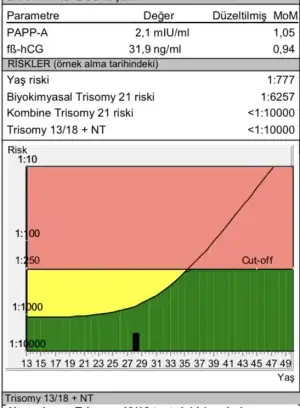

Benim doktorum genoksu önerdi canım 12. Haftamda kontrole gittiğimde orada alındı kan evede geliyorlar ama bildiğim kadarıyla bir bak istersen.kızlar bu evden kan alan iyi fetal dna firmaları hangileriydi. burda hangi,leri önerildi